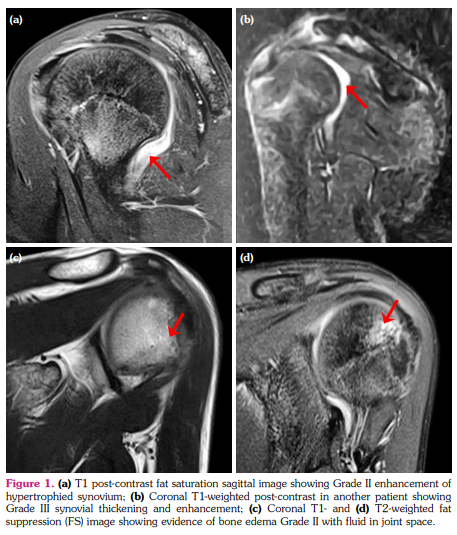

c) Cartilage lesion score: Nine (28.1%) joints in six patients showed cartilage lesions with a mean score of 0.3±0.6 (Figure 3a-d). Seven of these joints had Grade I and II joints had Grade II cartilage lesions (Figure 2a). The number of joints with cartilage lesions in sJIA and undifferentiated JIA were six (66.6%) and three (33.3%), respectively.

d) Bone erosion score: Bone erosions were seen in 15 (46.8%) joints in nine patients with a mean score of 0.6±0.8 (Figure 3e, f). Eleven joints had Grade I, three had Grade II, and one joint had Grade III bone erosion score (Figure 2a). The number of joints with bone erosions in sJIA, ERA, and undifferentiated JIA were 11 (73.3%), three (20%), and one (6.7%) joint, respectively.